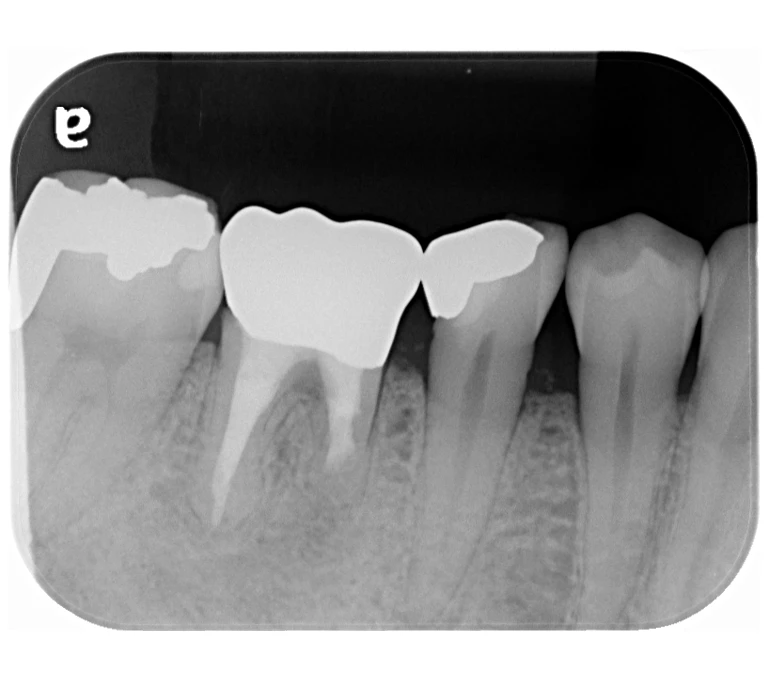

case 4.

治療前

治療後

| 主訴 | 右下奥歯が痛い。 他院で『膿の袋が大きいため抜歯』と言われセカンドオピニオン希望でご来院。 |

|---|---|

| 治療期間 | 約半年(6か月) |

| 治療費 | 約5万円 |

| 治療内容 | ラバーダム、マイクロスコープ下にて根管治療を実施し、歯根端切除を行う。歯茎の腫れは消失し違和感や痛みも消失した。 |

| 治療のリスク | マイクロスコープやCTを使用し、可能な限り精密な根管治療を行っていますが、歯根の形態や病変の大きさ、過去の治療履歴などにより、治癒が得られない場合があります。 また、治療後に再感染や歯根破折が生じることもあり、その場合は再治療や抜歯が必要となることがあります。 治療結果には個人差があり、すべての症例で同様の経過を保証するものではありません。 |